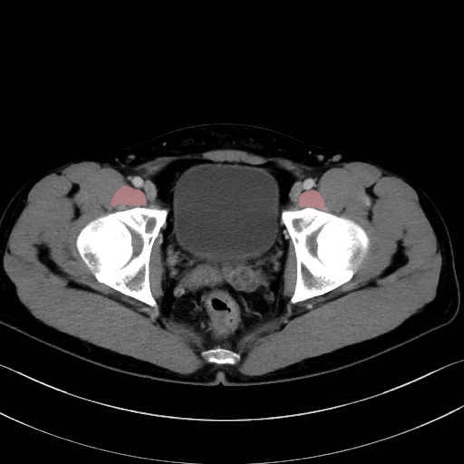

2. 腸腰筋群と骨盤底筋

大腰筋 (Psoas major)

腸骨筋 (Iliacus)

肛門挙筋 (Levator ani)